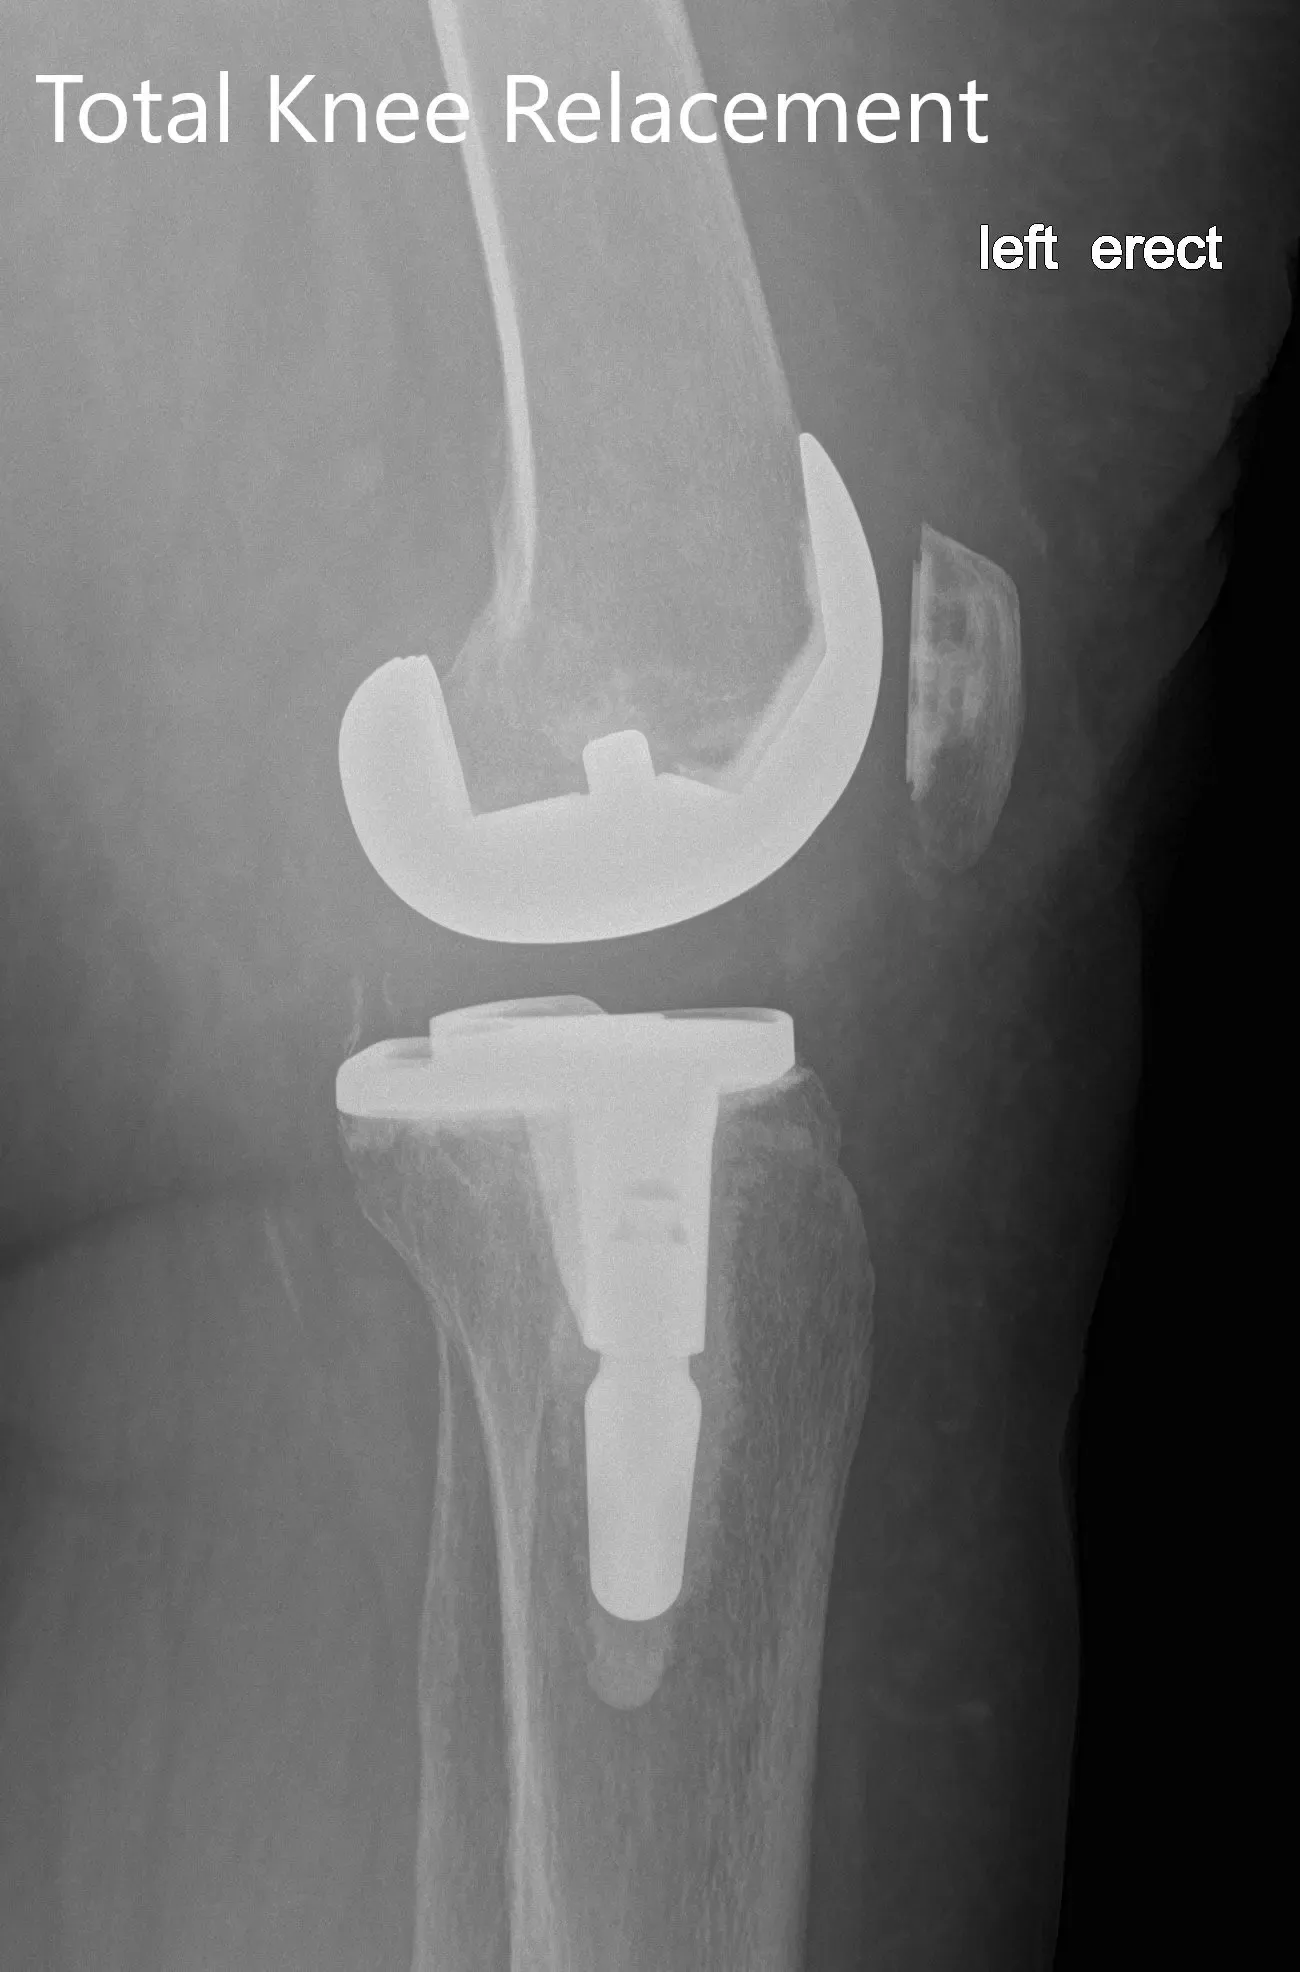

IMPLANTES UTILIZADOS: Estabilizado posteriormente, 8 componentes femorales estándar izquierdos lado izquierdo con tibia E izquierda cementada con tallo de 14 x 30 con poliuretano de 16 mm y polirotela de 29 mm de diámetro.

Radiografía postoperatoria de la izquierda mostrando la vista anteroposterior y lateral con prótesis total de rodilla en posición